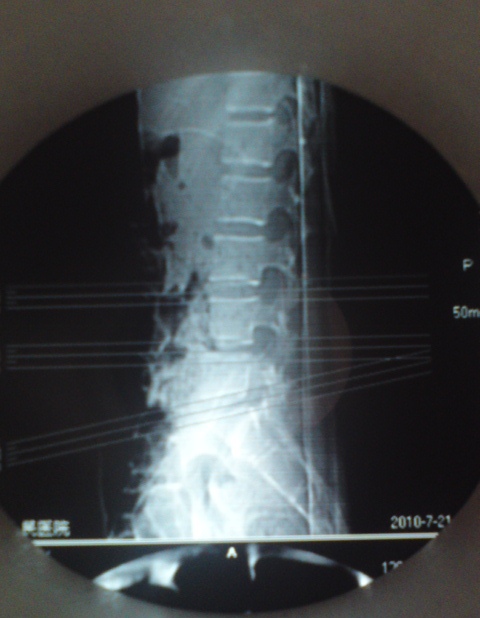

标题: CT27836:女 ,13岁,腰痛数月,加重一月,检查下腰部明显压 [打印本页]

标题: CT27836:女 ,13岁,腰痛数月,加重一月,检查下腰部明显压

考虑腰4椎体结核伴右侧椎旁及椎管右侧硬脊膜外脓肿形成。

骨质破坏+脓肿=结核

建议椎体扫描连续层面观察或mri看看,是脓肿还是软组织肿块,tb脓肿很少到后方来的,肺部有无tb灶。

考虑腰椎结核伴右侧椎旁及椎管右侧硬脊膜外寒性脓肿形成;建议必要时行mri检查。